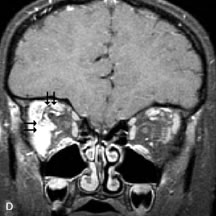

Inflammatory conditions of the orbit, both idiopathic (inflammatory pseudotumor) and those of known causes, have been found to be hypointense to fat and isointense to muscle on Tl-weighted studies and isointense or slightly hyperintense to fat on T2-weighted images (Fig. 21).50,64,69 The more fibrous or sclerosing varieties have less signal intensity on T2-weighted images. Marked enhancement is seen in pseudotumor infiltrates after gadolinium administration.70 The same signal characteristics are demonstrated in patients with Tolosa-Hunt syndrome, with mass lesions seen in the cavernous sinuses and orbital apices.71

Fig. 21. A. T1-weighted MR scan demonstrates diffuse enlargement of both the superior rectus and levator palpebrae superioris muscles (single arrows). The involvement of the tendinous insertions and preseptal soft tissues (open arrows) as well as lack of involvement of other muscles helps differentiate this entity from thyroid-associated orbitopathy. B and C. Postcontrast fat-suppressed T1-weighted MR scans demonstrate extensive enhancement of the involved muscles as well as the preseptal (open arrows) and perinuscular tissues (double arrows).